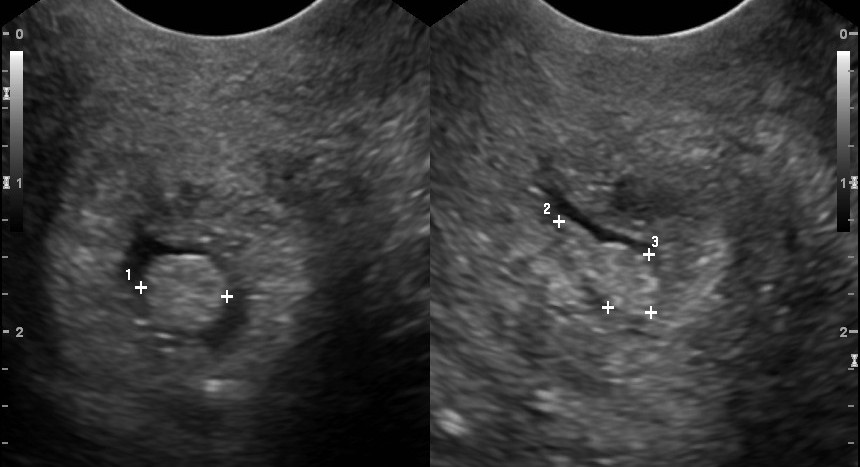

초음파를 통해 보이는 자궁경부 폴립

자궁경부 폴립은 골반 내진을 통해 자궁경관에서 빨갛거나 보랏빛을 띄는 돌출부를 관찰하여 진단할 수 있다.[13][7] 생검을 통해 세포가 확연히 들어나면 진단이 확정된다.[13]